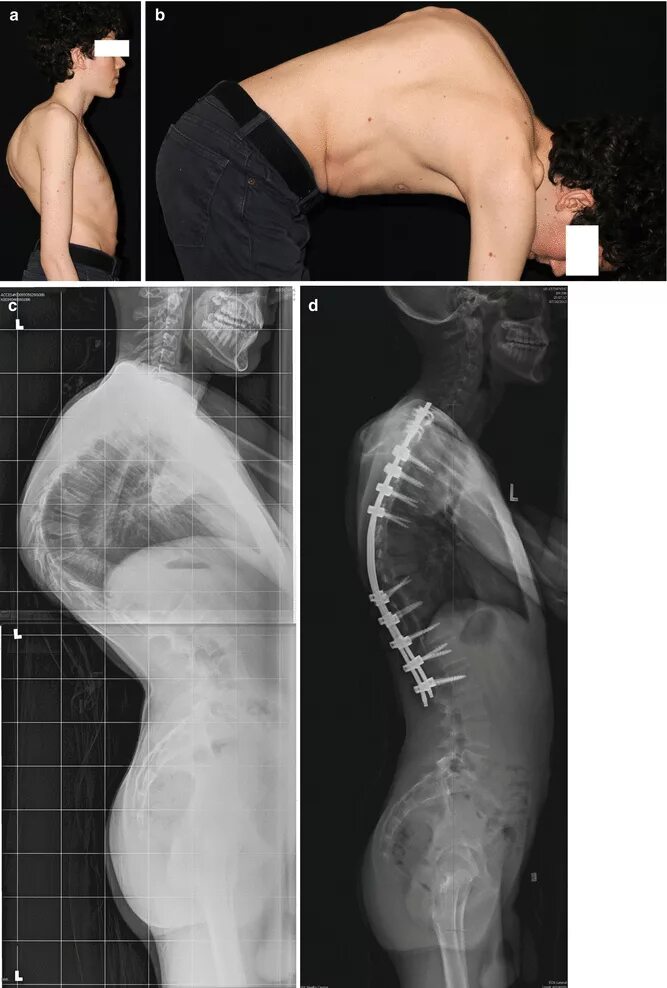

Болезнь шейермана мау что